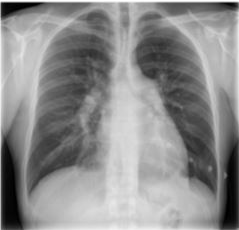

Um homem de 62 anos de idade, previamente hipertenso, refere que estava compensado e assintomático quando começou, há cinco meses, com dispneia aos esforços, após uma sensação de opressão no tórax, que melhorava parcialmente com o repouso e que perdurou cerca de cinco dias. Ele não procurou o serviço médico na época. Nega tosse, expectoração ou chiado. Nega tabagismo. Exame físico: PA de 140 x 76 mmHg; FC de 86 bpm; e saturação de O2 (ar ambiente) de 91%. Ausculta cardíaca: hiperfonese e desdobramento de segunda bulha em foco pulmonar. Turgência jugular bilateral. Presença de estertores bibasais e de edema de membros inferiores. Exames laboratoriais: hemoglobina 12,2 g/dL; leucócitos 8.500/mm3; e plaquetas 152.000/mm3. Realizou, também, a radiografia de tórax reproduzida a seguir.

Com base nesse caso hipotético, é correto afirmar que o exame indicado para se iniciar a investigação da dispneia do paciente é o(a)